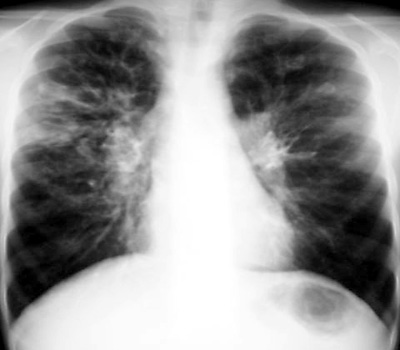

Cystic Fibrosis (CF)

Cystic Fibrosis is an autosomal recessive disease affecting 1/1500 caucasian individuals. The pulmonary system is most severely affected, but gastrointestinal complications are also common with meconium ileus in the newborn period and malabsorption that can result in failure to thrive.

Supportive care for CF has greatly extended the quality of life and overall life expectancy for these patients. However, recurrent pulmonary infections in combination with malnutrition will eventually lead to pulmonary insufficiency and pulmonary hypertension.

The presence of multiple recurrent pulmonary infections should lead to a test for CF. Meconium ileus is virtually the only diagnostic presentation of CF in the early course of the disease. Eventually, the CXR will demonstrate the characteristic hyperinflation and bronchiectasis. The CXR is used primarily to monitor acute infections and the general progression of the disease.